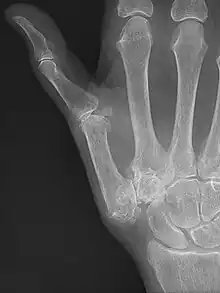

| Osteoarthritis of the trapeziometacarpal joint | |